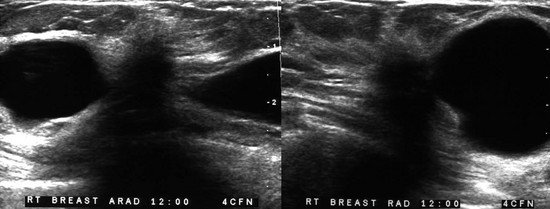

CASE 8-9. A 41-year-old woman with a history of bilateral cysts had screening mammography performed 2 months ago that showed extremely dense tissue with multiple bilateral benign-appearing masses. There were no suspicious findings (BI-RADS 2).

She now presents with a new palpable mass in her upper right breast and is referred for US. Your sonographer brings you the following images from the palpable region. What do you recommend?

CASE 8-9. There are multiple cysts. Did you notice the hypoechoic shadowing region on the lower right image? You rescan this region and find a hypoechoic solid shadowing mass with spiculated margins, adjacent to cysts. This is highly suspicious. Diagnosis: IDC.